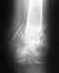

Re: несрастающийся перелом бедра

послал Анастасия 24 Июль 2011, 21:03

Прилагаю последние снимок. Спасибо